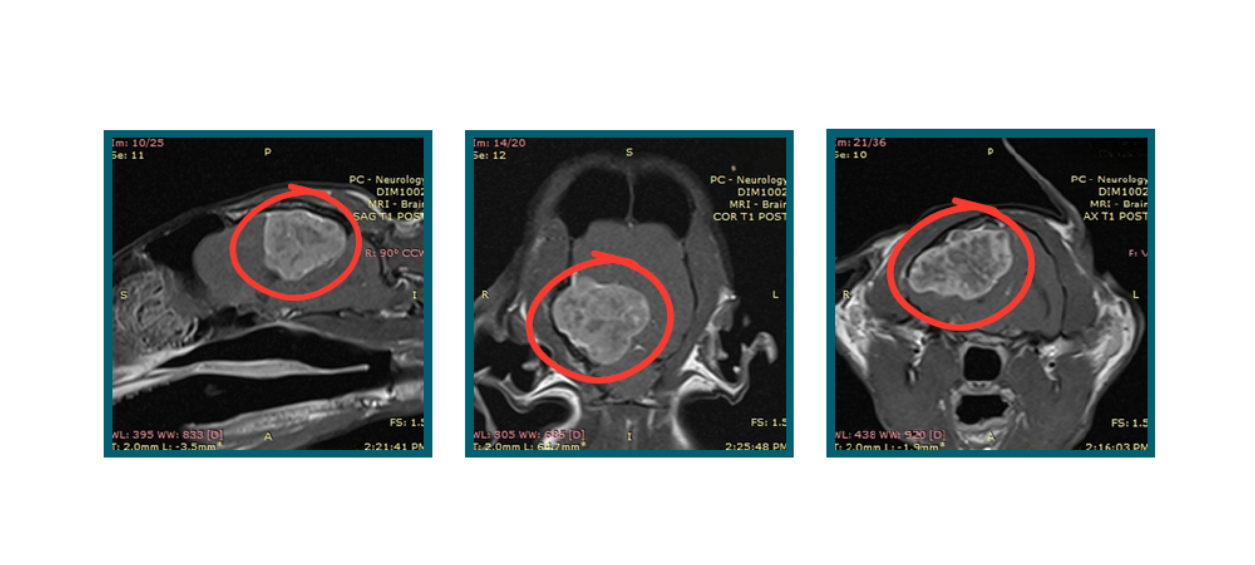

On the day of initial presentation, Mr. Collins had an MRI performed which demonstrated a large tumor compression in his right temporal and occipital lobes. These findings were suggestive of a primary brain tumor called a meningioma. He was treated with steroids while surgical options were considered by his family.